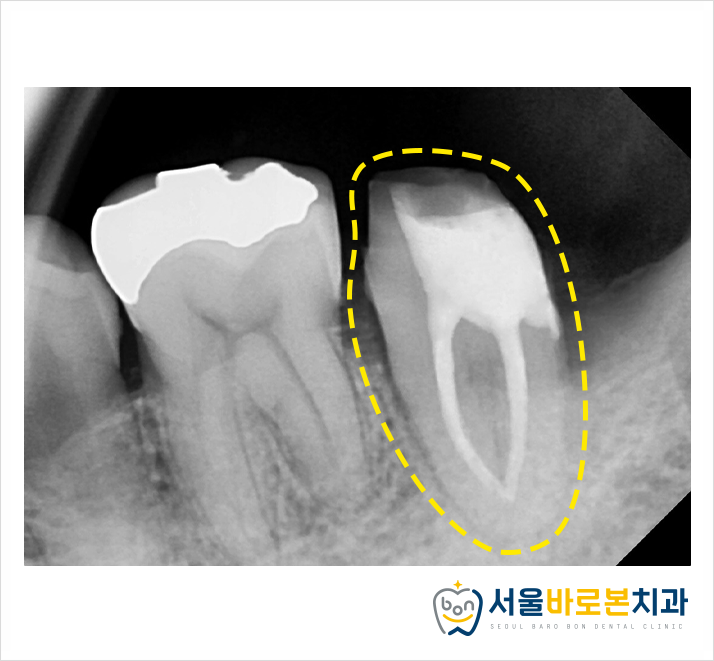

그 다음, 어금니에 충치를 제거한 부위에

보강 재료를 쌓아 올렸고,

엑스레이 사진을 통해

체크를 해주고 있는 모습입니다.

더불어 사랑니는

잇몸에 부분적으로 매복되어 있었기에

잇몸을 일부 절개하고 열어서

분할 발치를 진행했습니다.

그리고 앞의 큰 어금니는

신경치료와 잇몸치료를 진행하였고,

현재 보철물 제작을 위해

치아 외형을 다듬는 모습입니다.

* 큰 어금니 치아 뿌리에

치석과 염증이 심하여

잇몸치료도 병행해주었답니다.